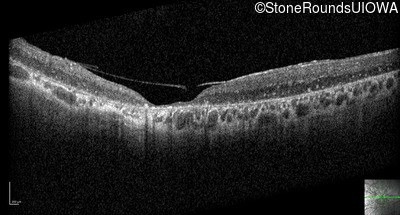

Optical Coherence Tomography - Right - 10/200

Exemplar / OCT Stack